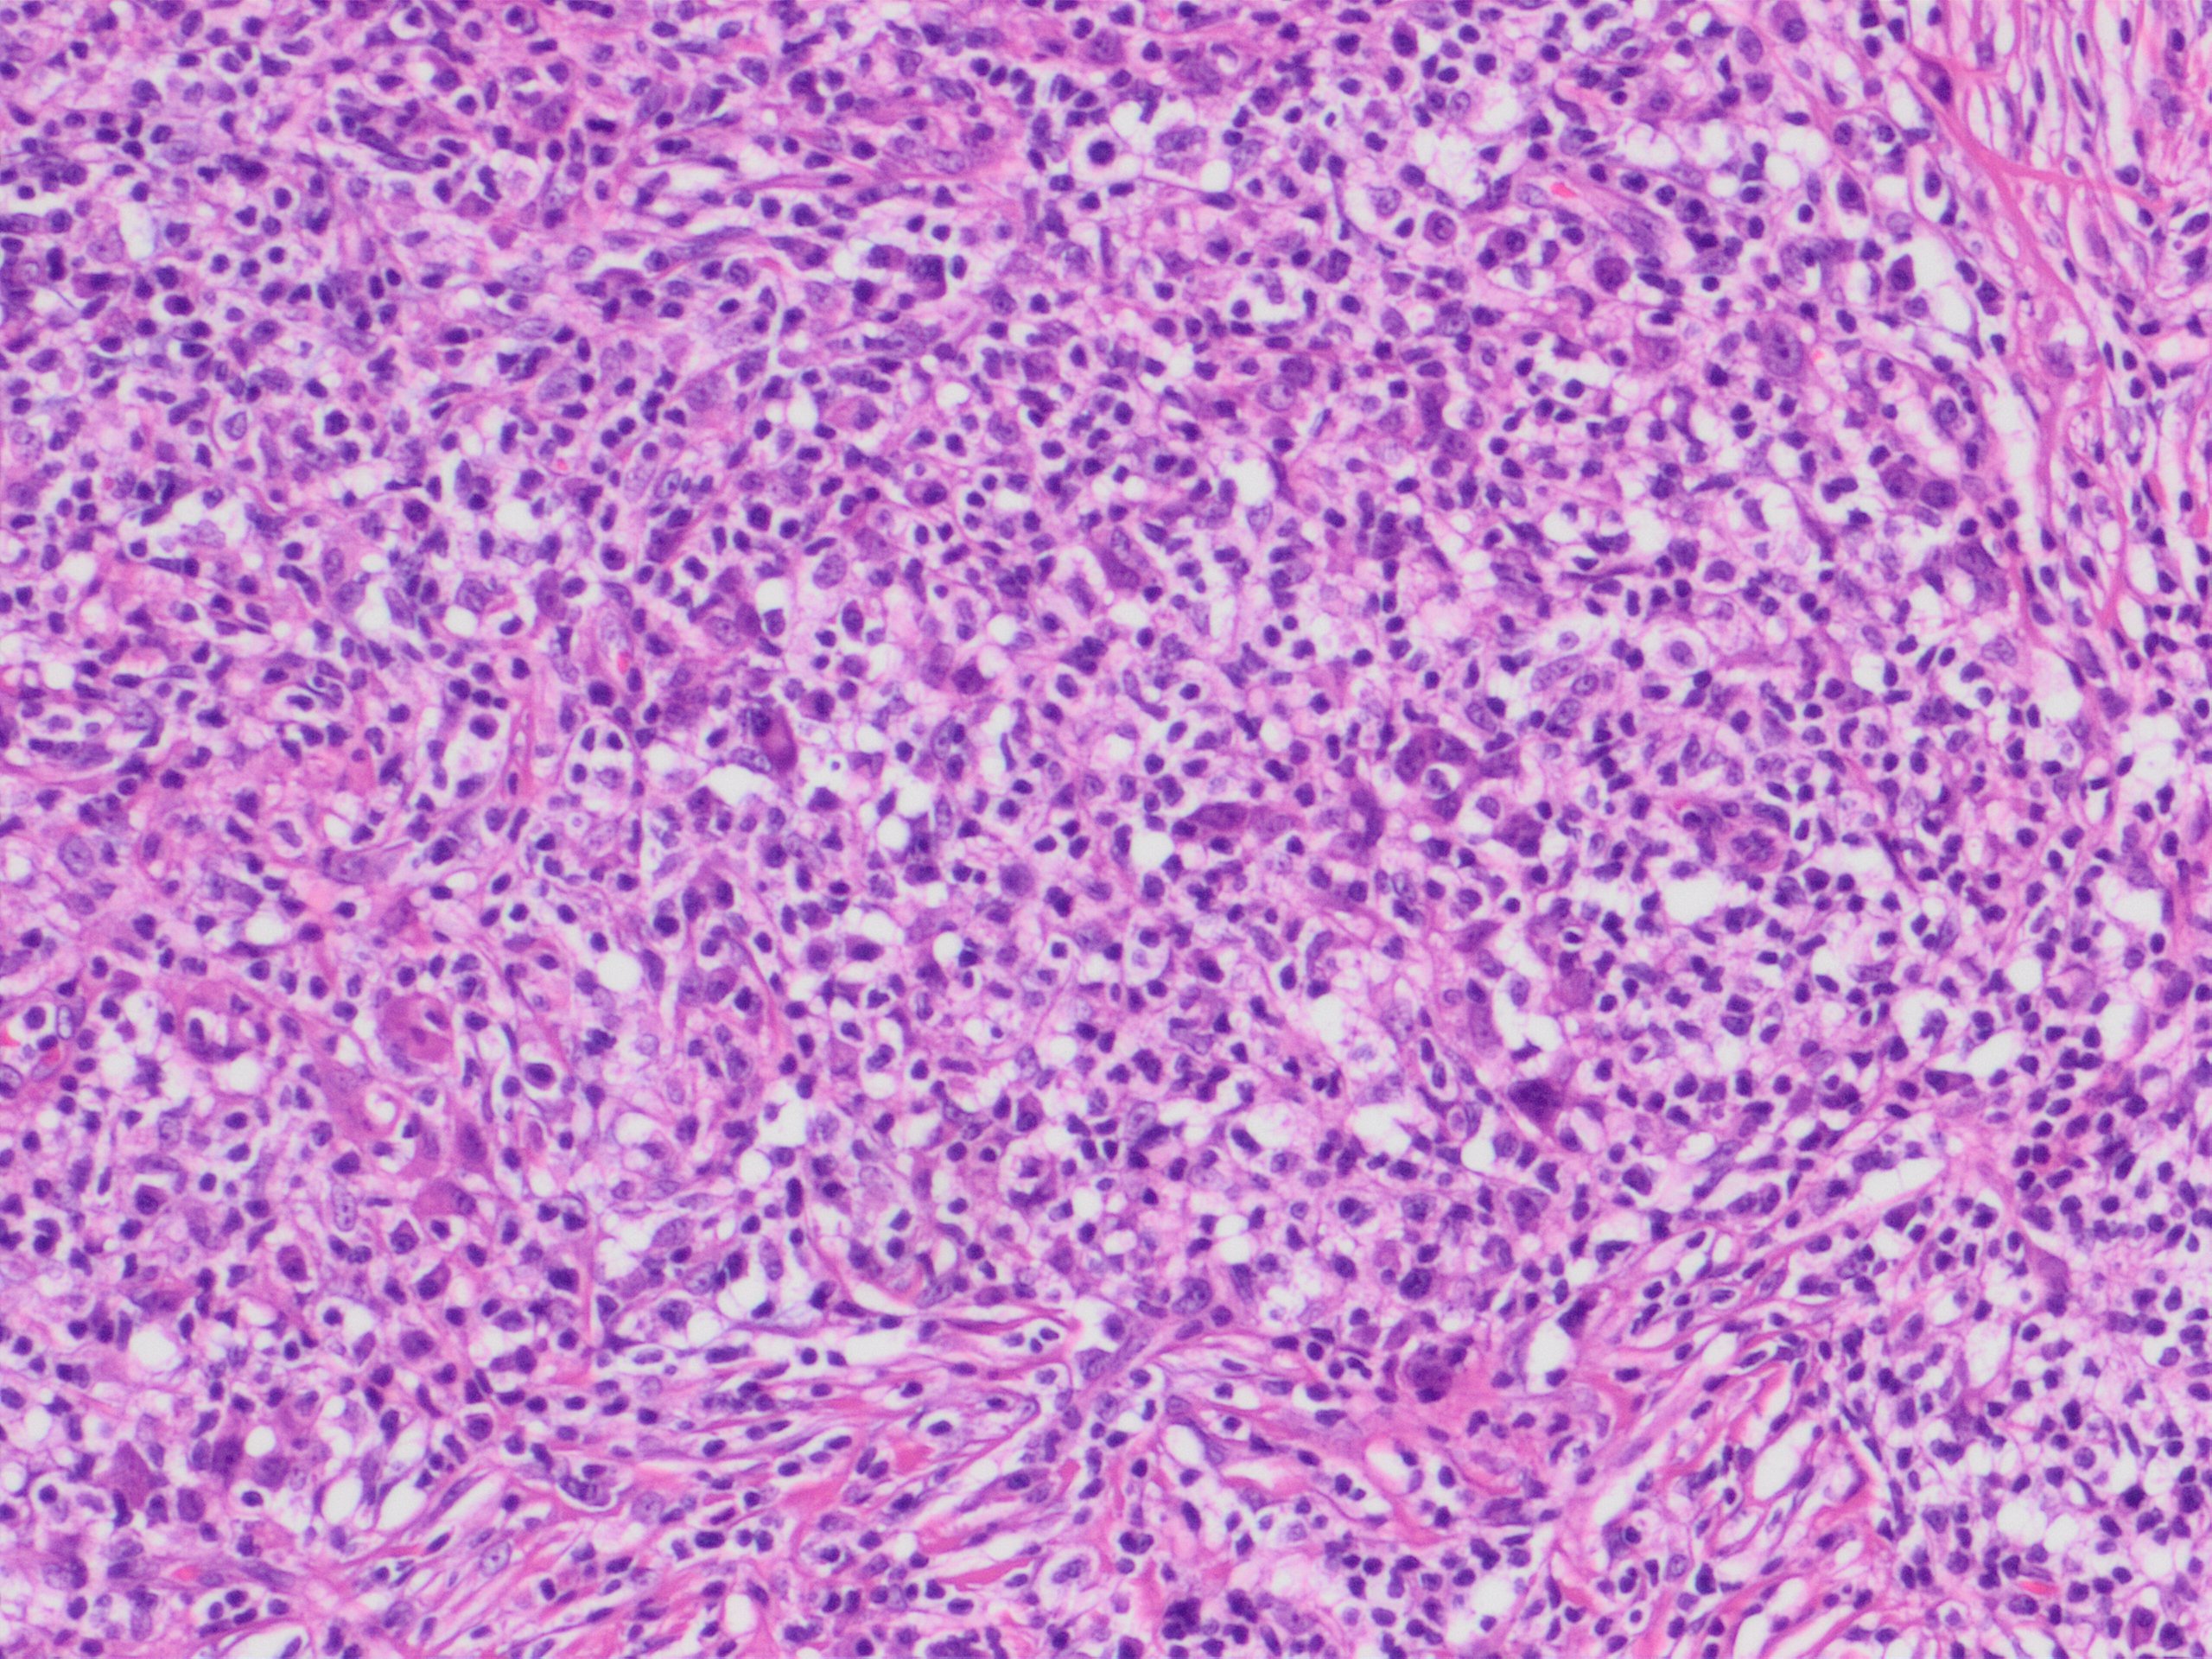

79-year old female with a two-month presentation of symmetric disseminated plaques and small erythemato-violaceous nodules. Has rheumatoid arthritis, diabetes mellitus and a slight monoclonal gammopathy. On methotrexate, leflunomide and other medications for years.

Link : https://amubox.univ-amu.fr/s/btgFTfH7pZenXX8